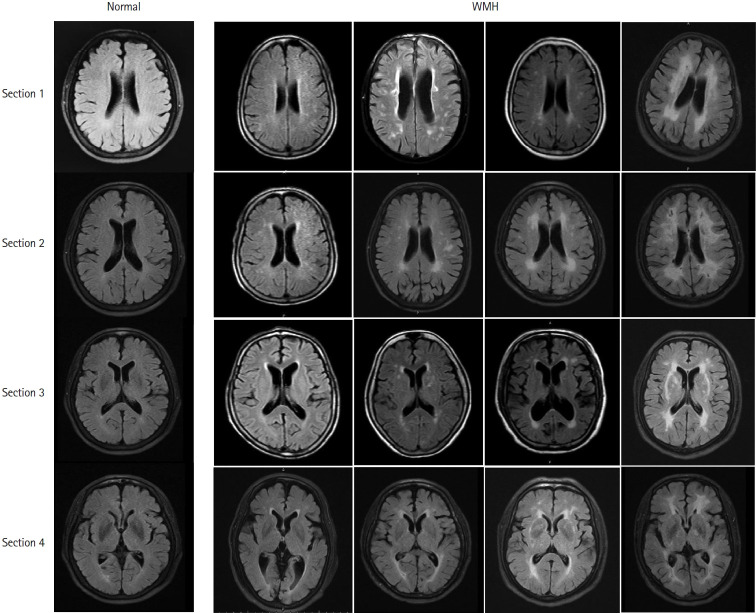

Leukoaraiosis (LA) manifests as cerebral white matter hyperintensities on T2-weighted magnetic resonance imaging scans and corresponds to white matter lesions or abnormalities in brain tissue. Clinically, it is generally detected in the early 40s and is highly prevalent globally in individuals aged >60 years. From the imaging perspective, LA can present as several heterogeneous forms, including punctate and patchy lesions in deep or subcortical white matter; lesions with periventricular caps, a pencil-thin lining, and smooth halo; as well as irregular lesions, which are not always benign. Given its potential of having deleterious effects on normal brain function and the resulting increase in public health burden, considerable effort has been focused on investigating the associations between various risk factors and LA risk, and developing its associated clinical interventions. However, study results have been inconsistent, most likely due to potential differences in study designs, neuroimaging methods, and sample sizes as well as the inherent neuroimaging heterogeneity and multi-factorial nature of LA. In this article, we provided an overview of LA and summarized the current knowledge regarding its epidemiology, neuroimaging classification, pathological characteristics, risk factors, and potential intervention strategies.